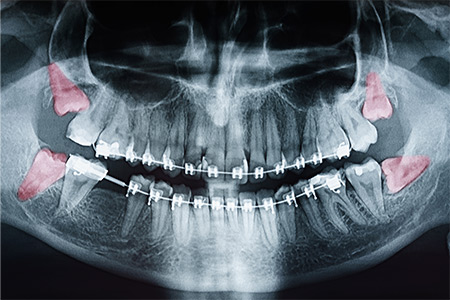

Pro-active removal of wisdom teeth before you experience any problems can help avoid painful complications down the road |

Your regular dentist may refer you to us to take a closer look at your particular situation and to get our experienced, professional opinion |